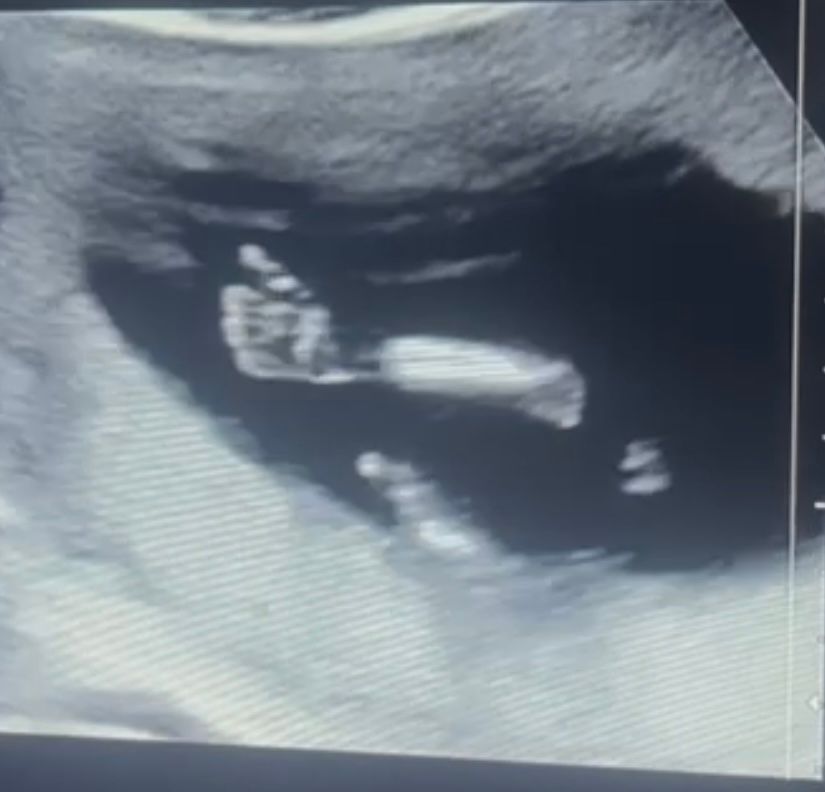

Сын меня успокаивает, как только начинаю думать о чем-то нехорошем (что вес не набираю совсем, что живот не растет вообще, в отличии от знакомых на том же сроке и т.д.) сразу дает знать, что все хорошо (по крайней мере я так думаю). До этого был большой палец вверх на узи, а теперь вот пинки 🥰